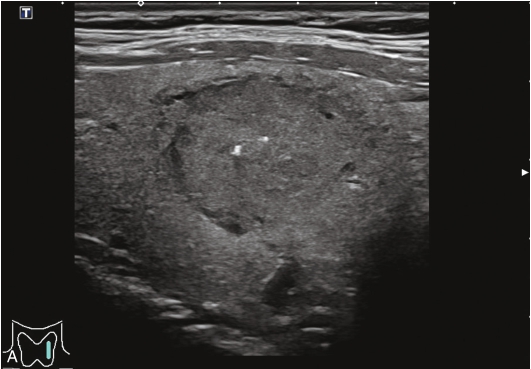

甲状腺右叶下极可见一低回声结节,紧贴甲状腺包膜,突出于甲状腺包膜,大小约0.82cm×0.72cm×0.55cm,呈椭圆形,边界清楚,内部为低回声,分布不均匀,后方回声稍增强,CDFI显示结节内未见明显血流信号,弹性成像示弹性评分为3分,见图1-3-11。

图1-3-11 甲状腺“木乃伊”结节

A、B、C、D.甲状腺“木乃伊”结节常规超声图像

经肘正中静脉团状注射造影剂SonoVue1.2ml后,13s周围甲状腺组织开始增强,病灶边缘部呈稍增强,病灶内部始终呈无增强,在整个造影过程中病灶内始终呈无增强,见图1-3-12、ER1-3-6。

“木乃伊”结节超声造影表现为无增强。

部分良性甲状腺结节囊液吸收后超声表现为低回声、缩小,超声表现为可疑恶性征像,二维超声表现与甲状腺乳头状癌难以鉴别,超声造影可以明确病灶内有无增强,提高诊断准确性。

图1-3-12 甲状腺“木乃伊”结节造影图像

A.造影示低回声结节呈无增强;B.增强晚期仍呈无增强